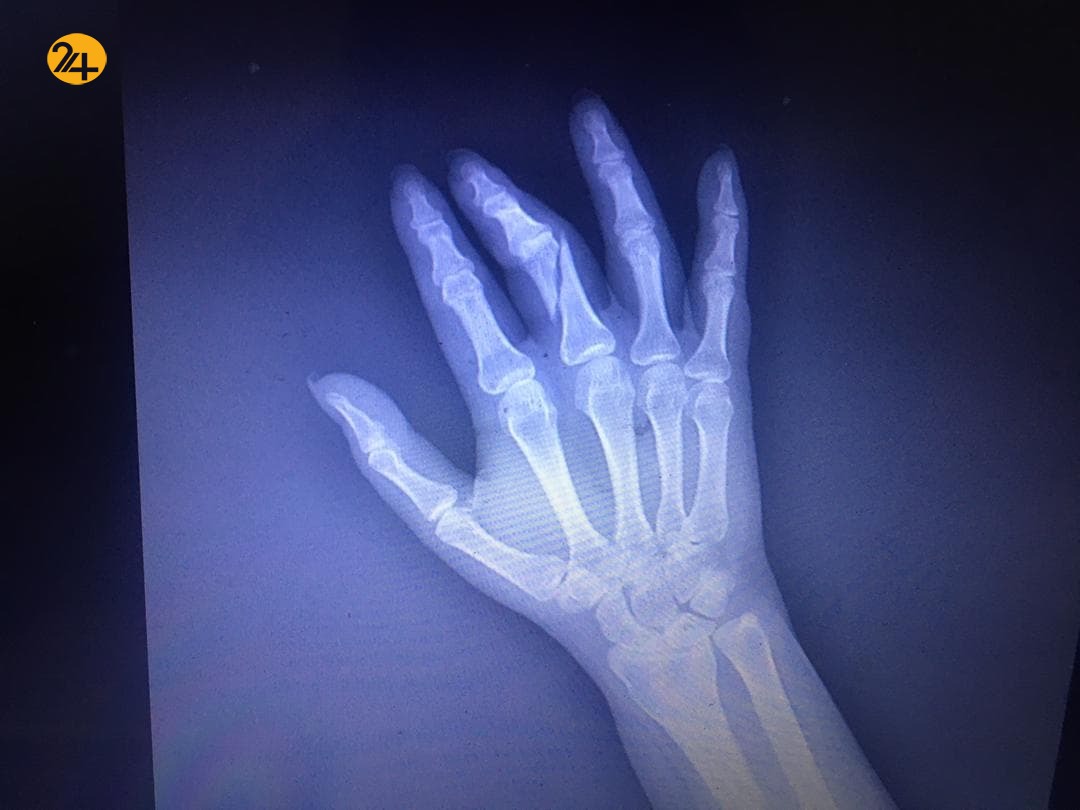

رویداد۲۴ یک دست شکسته و پین شد دستمزد خبرنگاری است که رفت تا بنویسد و به ما بگوید که در مراکز واکسیناسیون چه میگذرد. فائزه مومنی خبرنگار رویداد ۲۴ روز دوشنبه ۲۹ اردیبهشت در حالی که برای تهیه گزارش از روند واکسیناسیون به یکی از مراکز آن مراجعه کرده بود، با برخورد و حمله مامور حراست دانشگاه علوم پزشکی شهید بهشتی مواجه و دچار شکستگی شدید از ناحیه انگشت شد تا جایی که دستش به صورت اورژانسی در همان شب روز حادثه مورد عمل جراحی قرار گرفت.

ماجرای برخورد با فائزه مومنی به صحن علنی امروز مجلس نیز کشیده شد و خضریان نماینده تهران در سخنانی در این باره گفت: در دستان این خبرنگار خانم پیچ و مهره قرار گرفته است از آقای وزیر (بهداشت) درخواست اکید داریم با عوامل برخورد کنند، اگر اقدامی صورت نگیرد مجلس ورود پیدا میکند.

در برابر درخواستش مقاومت کردم، اما او با گرفتن دست و کیف من که به روی شانه راستم قرار داشت مرا به سمت سالن میکشید. در این بین دسته کیف باز شد و حراست کیف را در دست چپ و دست من را در دست راست خود فشار داده و آن را به شدت میکشید. دستم را که در اثر فشار به شدت درد گرفته بود بیرون کشیده و متوجه انگشتی شدم که تا خورده بود! آنجا بود که متوجه شدم برای دستم اتفاقی افتاده.

با وجود شکستن انگشتم از دادن کیفم خودداری کرده و اجازه خروج نمیداد. بعد از حدود ۴۵ دقیقه و تماس با نیروی انتظامی و طرح شکایت کیفم را پس گرفته و راهی کلانتری، پزشک قانونی و بیمارستان شدم. انگشتی که حالا استخوانش به دو نیم شده بود آماده جراحی شبانه شد.